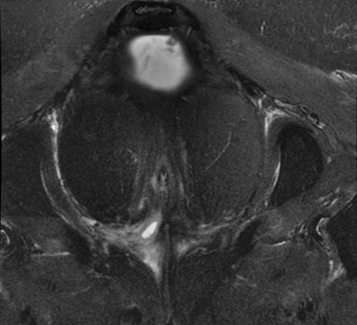

入院后第2日患者出现发热,体温最高39℃,无明显其他感染定位症状,抗生素治疗后仍有发热,复查hsCRP较前轻度升高(35.8mg/L~40.5mg/L),予抗感染治疗后高热仍反复。肛管MR增强检查显示“齿状线上方水平,约10~11点位置条片影经内外括约肌向右前下会阴皮下走行,外口不明确,局部与阴道紧贴,是否相通不明确;约10~11点位置另一条于内外括约肌间隙向右后上走行向直肠下段,似相通”(图1)。

图1  肛管MR增强